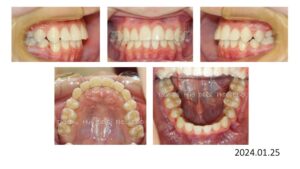

50歳の女性です。娘さんがうちで治療した数年後、自分も歯並びを治したいと希望され、治療を開始しました。

上下両側4番抜歯後、上下顎にブラケットを付け、

スペースクローズが終わり、細部の仕上げを行い、

治療期間 2年 7か月で動的治療を終了しました。

人前で笑えるようになりました、と、とても喜んで頂く事が出来ました。